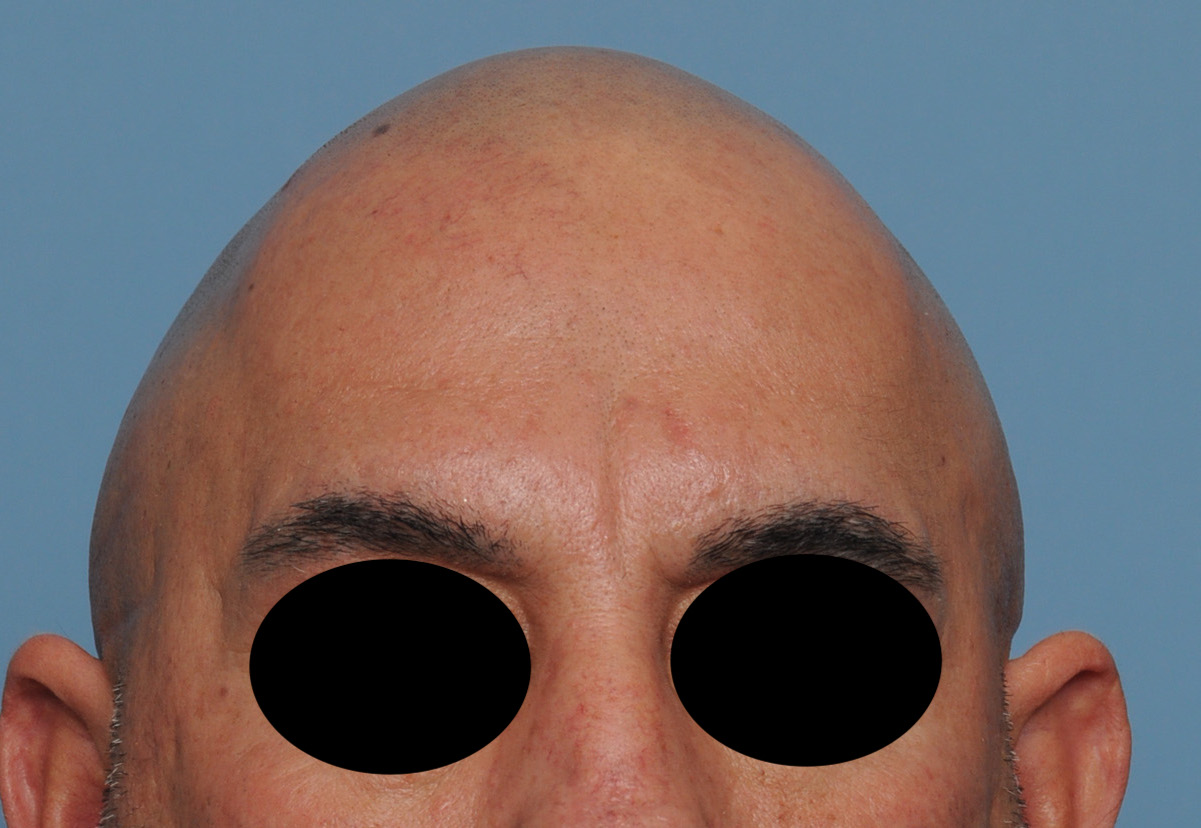

Patient 100

Desire for reshaping of an asymmetric flat back of the head in a shaved head male.

A combined back of the head reshaping procedure was done with a custom skull implant, sagittal ridge reduction and a right temporal muscle reduction.

Desire for reshaping of an asymmetric flat back of the head in a shaved head male.

A combined back of the head reshaping procedure was done with a custom skull implant, sagittal ridge reduction and a right temporal muscle reduction.